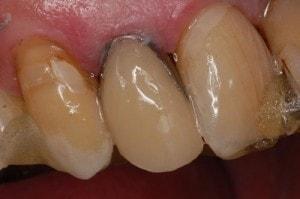

Caries in incisor teeth

Decay in teeth #'s 7, 8, and 10

Immediate objective is to manage the more serious cavities, and then address periodontal issues.

Restoration complicated by overlap